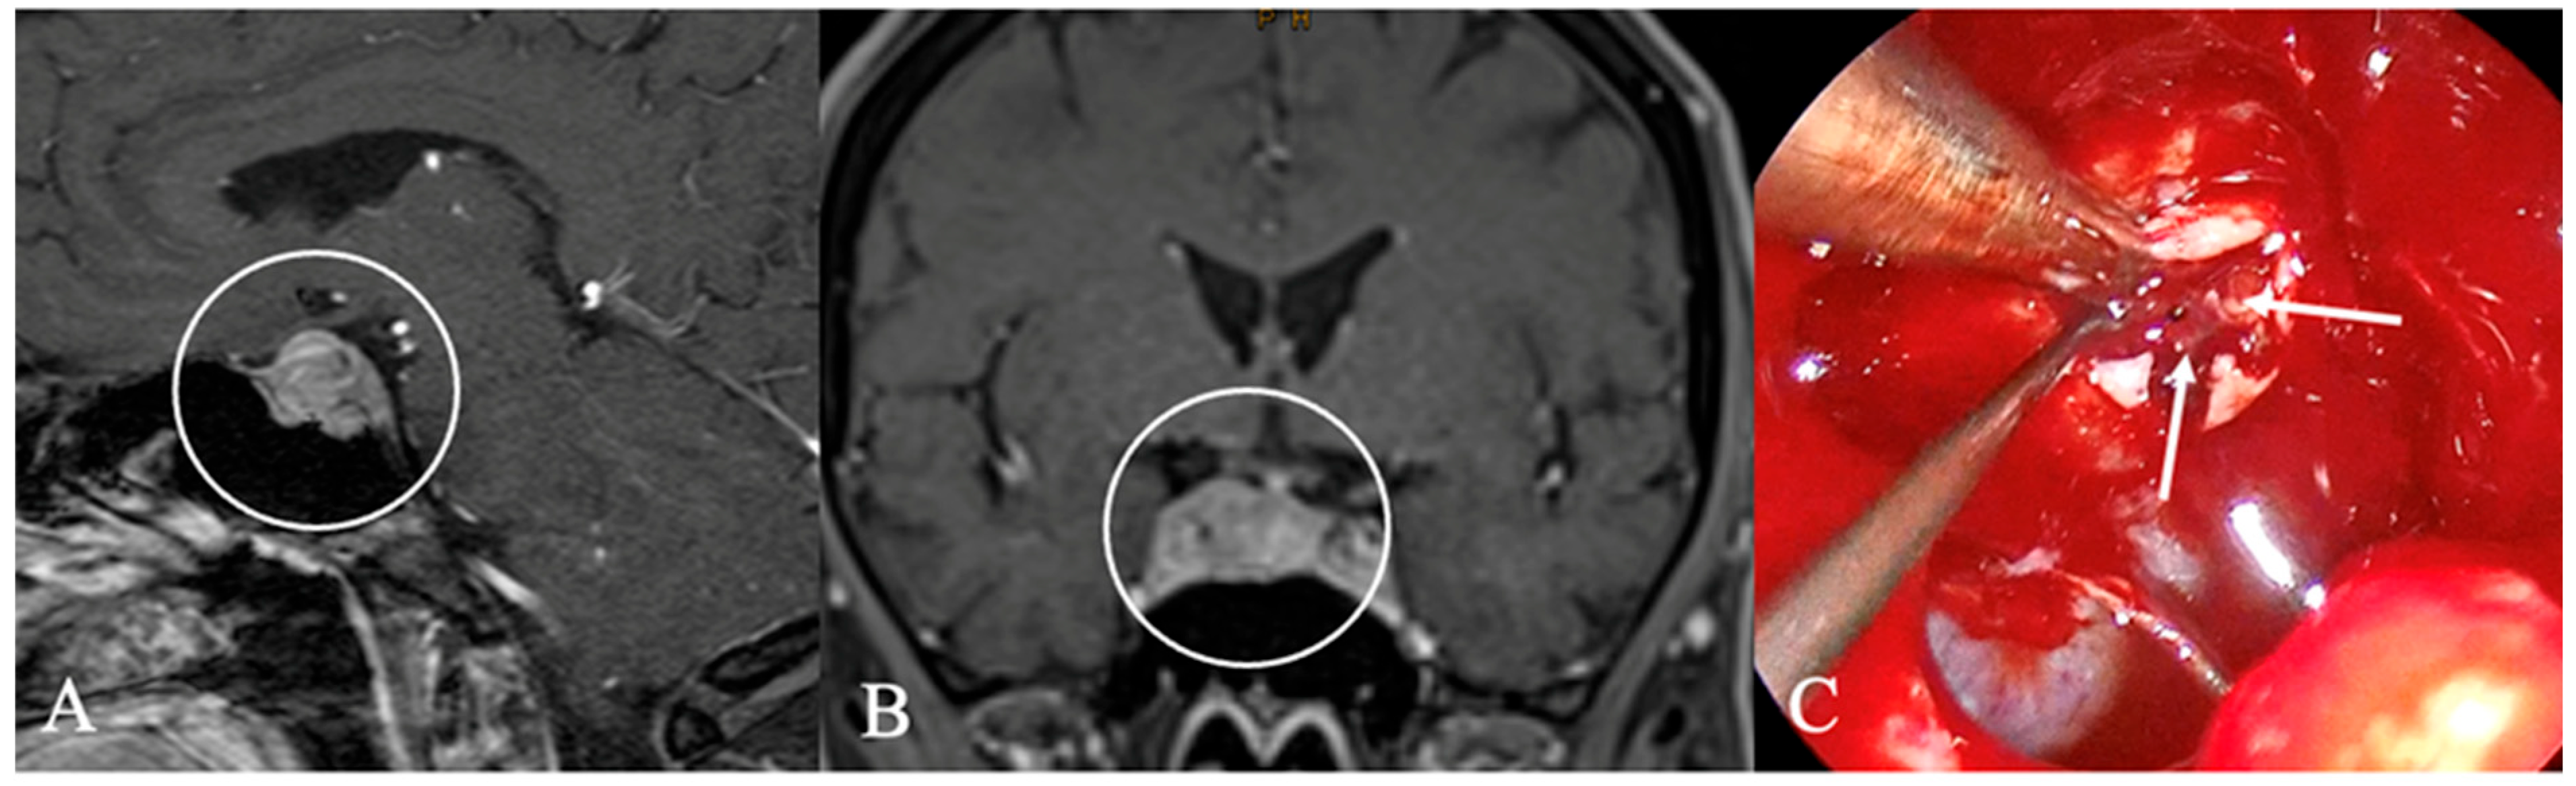

4.2. Differential Diagnoses and Case Presentations